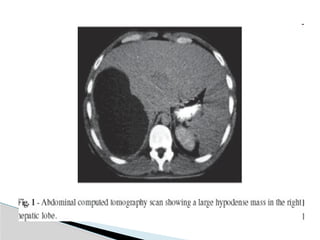

Computed Tomographic Scan

(Sensitivity 95%-100%)

 Well-demarcated areas hypodense to the

surrounding hepatic parenchyma.

 Peripheral enhancement is seen when IV contrast is

administered.

 Gas can be seen in as many as 20% of lesions.

 CT scan is superior in its ability to detect lesions less

than 1 cm.

 This technique also enables the evaluation for an

underlying concurrent pathology throughout the

abdomen and pelvis. Indium-labeled WBC scans are

somewhat more sensitive in this regard.